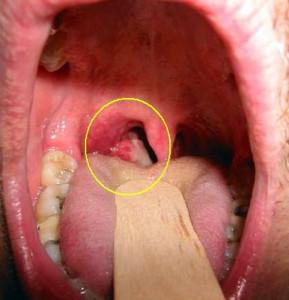

Опухоль гортани отличается от других онкологических заболеваний экзофитным ростом, то есть ростом наружу. При обследовании она выглядит как образование с нечеткими границами и может иметь форму сосочка или бугорка. В некоторых случаях опухоль проявляется в виде язв. В крайне редких ситуациях она может расти внутри тканей.

Следует обратить внимание на появление шишек на слизистой и кровянистые выделения – это могут быть первыми признаками воспалительного процесса.

Далее специалисты проводят осмотр горла и рта на наличие опухолей с использованием специальных инструментов и ларингоскопа.